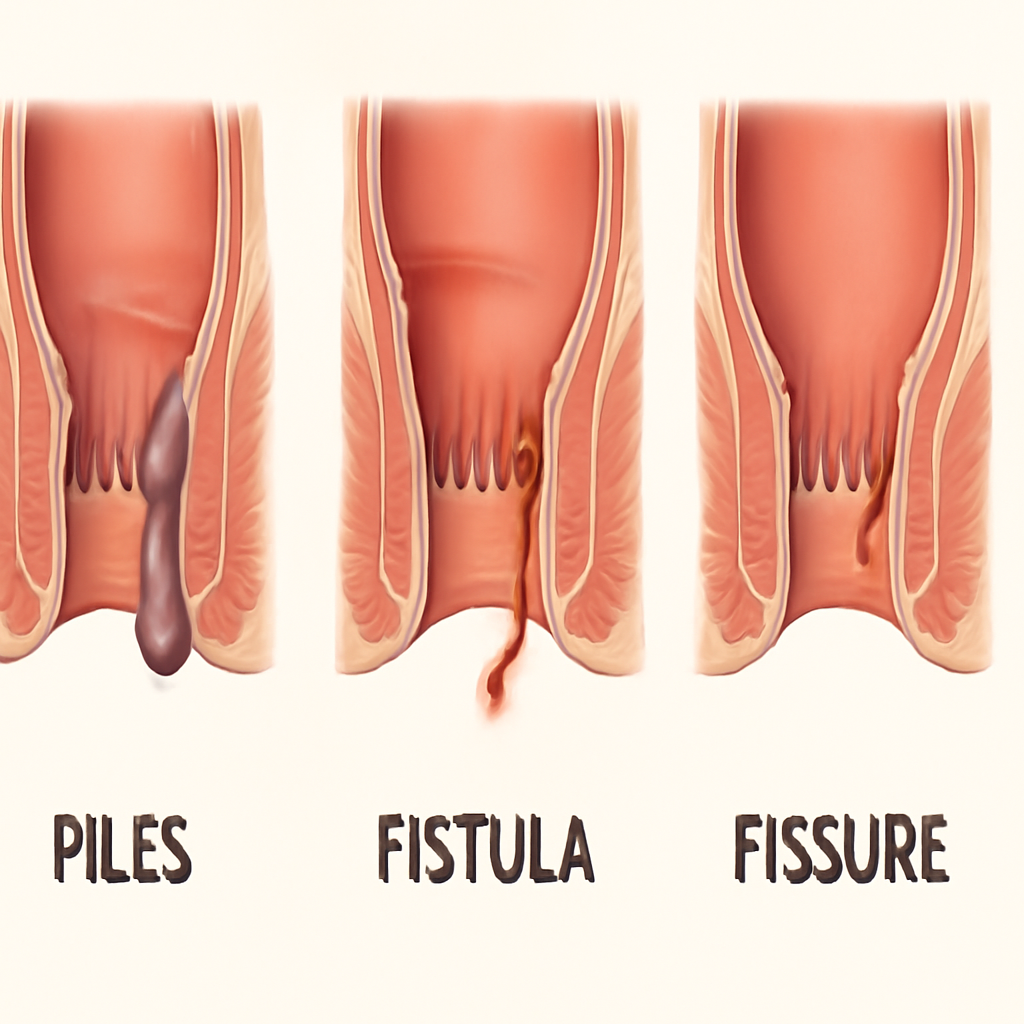

# Anal and Digestive